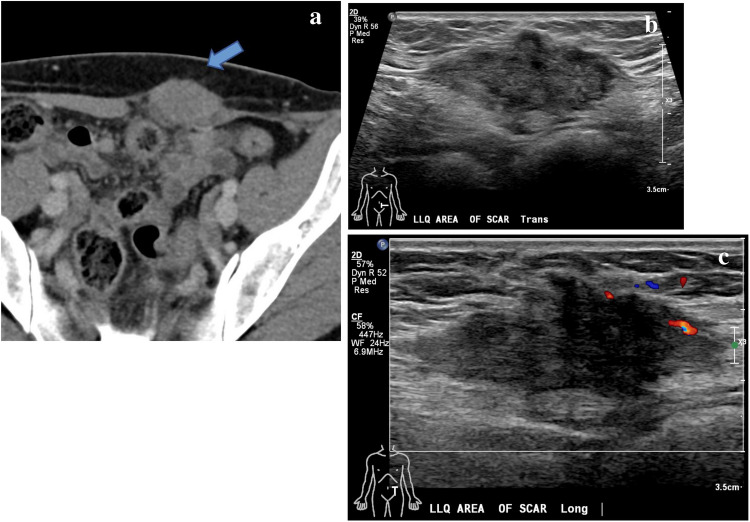

颗粒细胞瘤是一种罕见的源于雪旺细胞的软组织肿瘤。颗粒细胞瘤发生于前腹壁极为罕见,医学文献迄今仅报道了12例良性腹壁颗粒细胞瘤。我们报告一例上腹壁颗粒细胞瘤在最近产后35岁的妇女。根据患者的病史、近期产后表现和影像学表现,软组织肿瘤最初怀疑为硬纤维瘤。因此,在活检和切除后,良性颗粒细胞瘤的最终组织病理学诊断是非常罕见的。在此,我们讨论良性颗粒细胞瘤的独特表现及其诊断检查,包括影像学和组织病理学结果,以强调这种罕见实体在某些腹壁软组织肿块鉴别诊断中的可能性。

Granular cell tumors are uncommon soft tissue neoplasms derived from Schwann cells. It is extremely rare for granular cell tumors to be found in the anterior abdominal wall, with only 12 cases of benign abdominal wall granular cell tumors reported in the medical literature to date. We report a case of an upper abdominal wall granular cell tumor in a recently postpartum 35-year-old woman. Based on the patient's history, recent postpartum presentation, and imaging findings, the soft tissue tumor was initially suspected to be a desmoid tumor. Therefore, following biopsy and resection, the final histopathological diagnosis of benign granular cell tumor was quite unusual. Herein, we discuss a unique presentation of benign granular cell tumor and its diagnostic workup, including imaging and histopathologic findings, to highlight the possibility of this rare entity in the differential diagnosis of certain abdominal wall soft tissue masses.